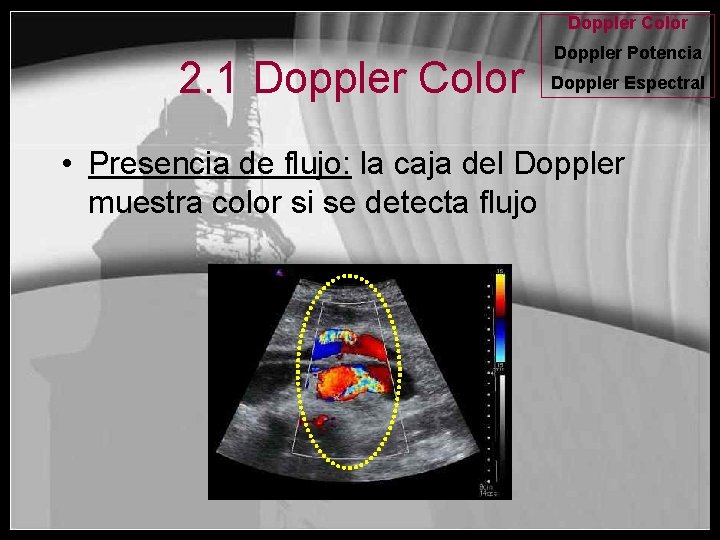

Doppler Color 2. 1 Doppler Color Doppler Potencia Doppler Espectral • Presencia de flujo: la caja del Doppler muestra color si se detecta flujo